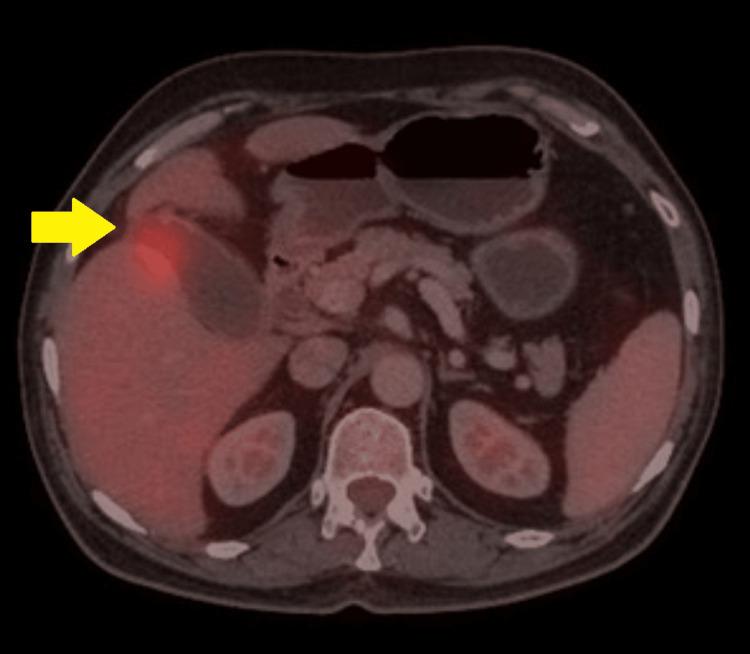

Malakoplakia, a rare granulomatous inflammatory condition, typically manifests in the genitourinary system. Its occurrence in the gallbladder is exceptionally uncommon, posing significant diagnostic challenges. A 68-year-old male presented with recurrent epigastric pain, and a suspicious gallbladder mass was found on imaging. He then underwent surgery due to concerns for malignancy. Histopathology of the surgical specimen revealed malakoplakia, highlighting the diagnostic dilemma encountered in such instances.

软斑病是一种罕见的肉芽肿性炎症性疾病,通常表现在泌尿生殖系统。其在胆囊中的发生极为罕见,带来了重大的诊断挑战。一名68岁男性因反复上腹部疼痛就诊,影像学检查发现胆囊有可疑肿块。由于担心是恶性肿瘤,他随后接受了手术。手术标本的组织病理学检查显示为软斑病,凸显了此类病例中遇到的诊断困境。